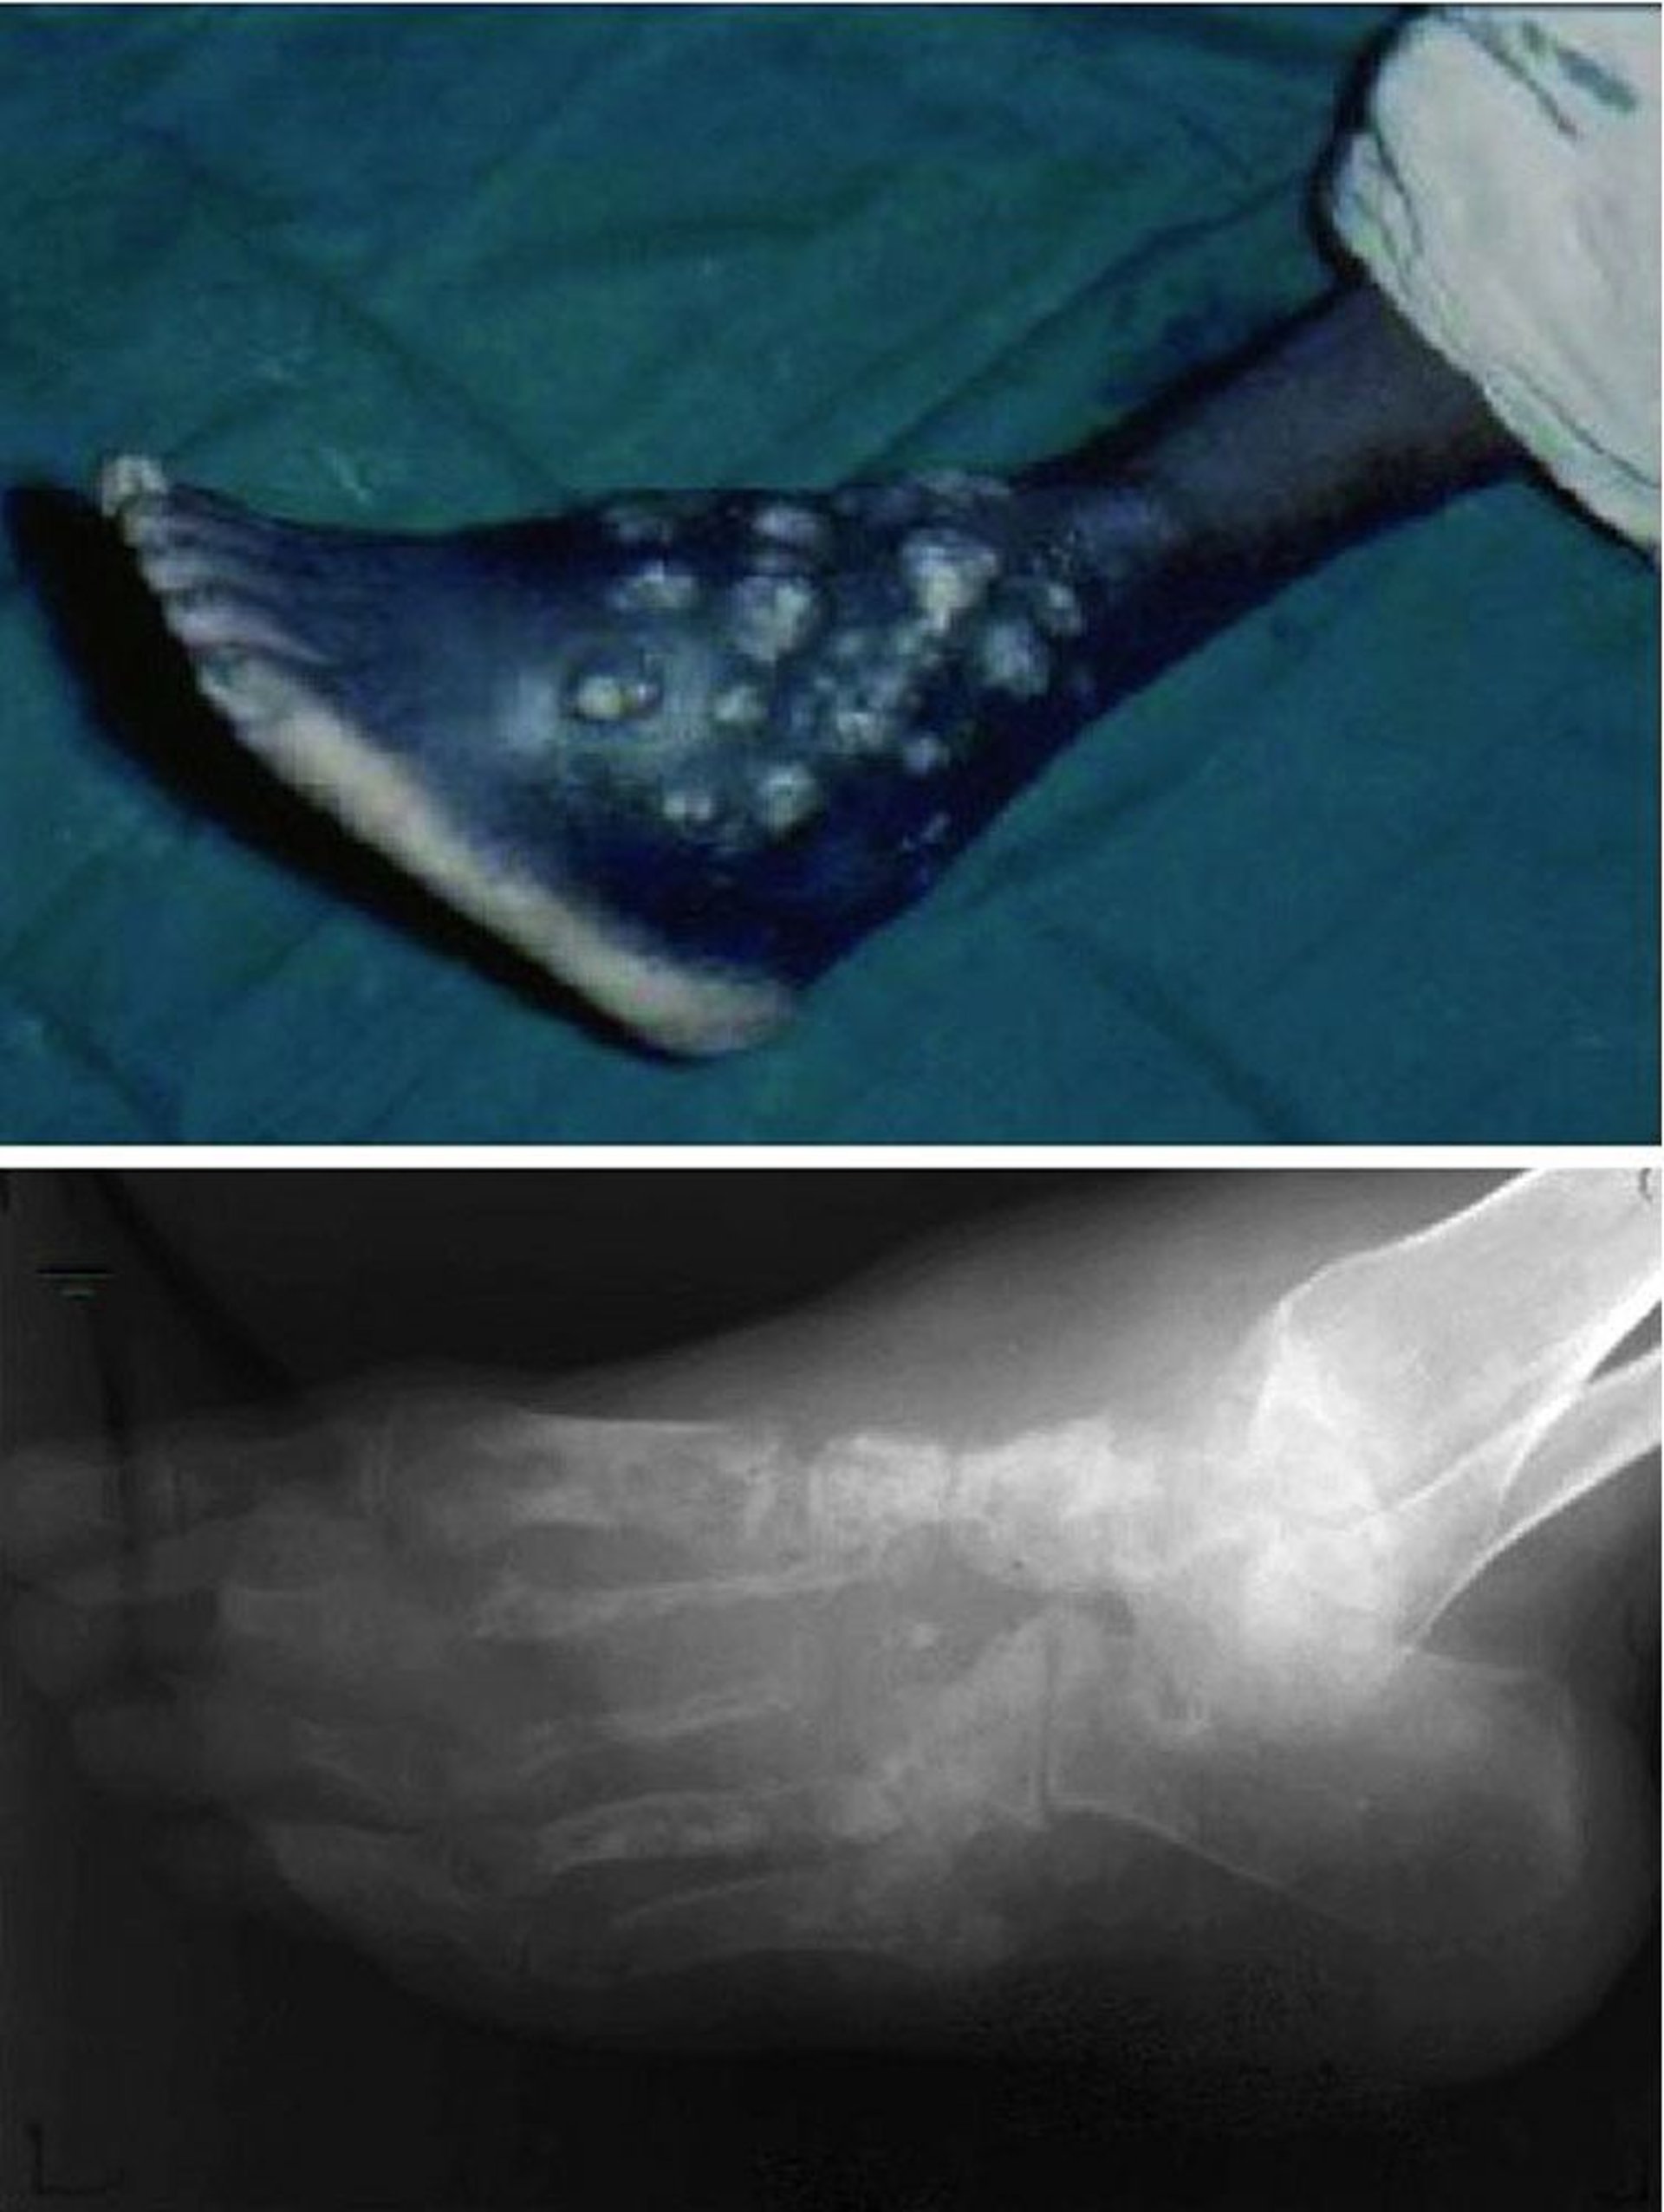

Mycetoma (Madura Foot)

This photo shows chronic, nonhealing wounds with recurring episodes of drainage and ulceration (top) and advanced destruction of the entire bony architecture of the foot (bottom).